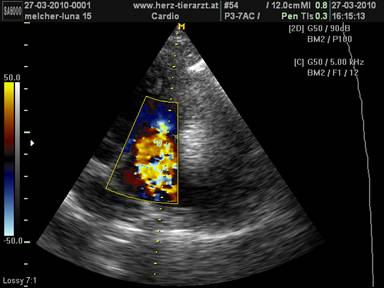

L’ecografia e’ il metodo migliore e piu’ moderno per diagnosticare una malattia cardiaca in cani e gatti; il veterinario si e’ specializzato in questa disciplina, offriamo anche EKG e raggi X. L’ambulatorio si trova a Villach (Austria) 30 Km da Tarvisio. Per effettuare l’esame cardiaco si prega di prenotare al numero: 0043 676 66 080 52; si parla tedesco, inglese e francese ma purtroppo non l’italiano.Per informazione su come raggiungere l’ambulatorio si prega di premere “Ort&Zeit” o di inserire l’indirizzo “9500 Villach, Maria Gailer Strasse 16” nella pagina: http://maps.google.it/. Si informa che il pagamento e’ richiesto in contanti.

Benvenuti nella pagina principale di ecografia e diagnostica cardiaca! |